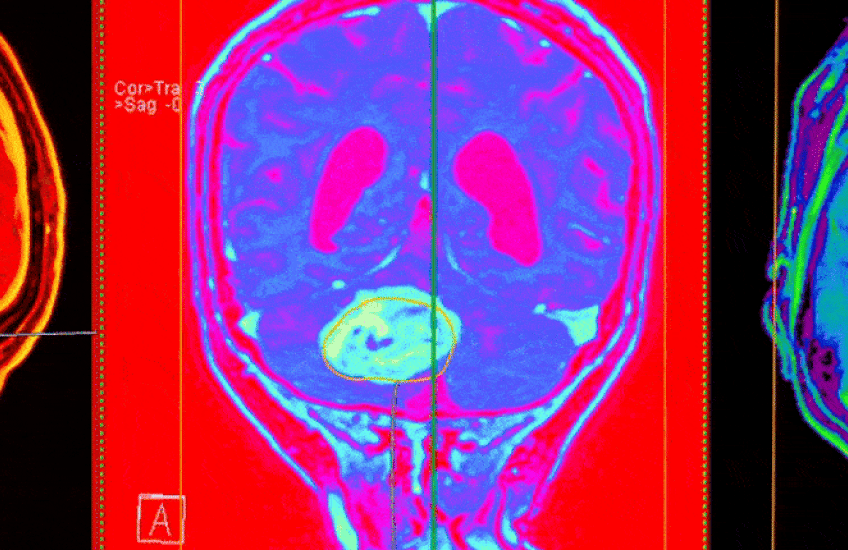

The tool, called PICTURE (Pathology Image Characterization Tool with Uncertainty-aware Rapid Evaluations), distinguished with near-perfect accuracy between glioblastoma — the most common and aggressive brain tumor — and primary central nervous system lymphoma (PCNSL), a rarer cancer often mistaken for glioblastoma. While both can appear in the brain, glioblastoma arises from brain cells, whereas PCNSL develops from immune cells. Their similarities under the microscope often lead to misdiagnosis, with serious consequences for treatment.

The model — which Yu developed with study co-first authors Junhan Zhao and Shih-Yen Lin — was evaluated on 2,141 brain pathology slides collected worldwide, including rare cases across both frozen sections and formalin-fixed samples. It was designed to spot critical cancer features including tumor cell density, cell shape, and presence of necrosis.

In tests, the PICTURE model correctly distinguished glioblastoma from PCNSL more than 98 percent of the time — a level of accuracy that held up when tested in five independent international patient groups. In addition, PICTURE identified samples belonging to 67 CNS cancers that were neither gliomas nor lymphomas.

The model could spot tumors it had not seen during its training and, when it did, it raised a red flag for human review. In other words, the tool knew when it didn’t know, Yu said, and this prevented the system from pigeonholing unclear cases into known categories. This feature renders the model unique among other AI systems, the researchers said. In comparison, other AI tools can differentiate in a binary, either-or fashion — disease A versus disease B. This is especially problematic for brain pathology, Yu noted, because there are more than 100 different subtypes of brain cancers, and many of them are relatively rare.

PICTURE outperformed human pathologists in hard-to-distinguish tumors in the brain. In tests, human specialists showed significant disagreement on difficult diagnoses, with some tumor types misdiagnosed 38 percent of the time. PICTURE correctly identified all these cases, offering support when expert opinion varies.